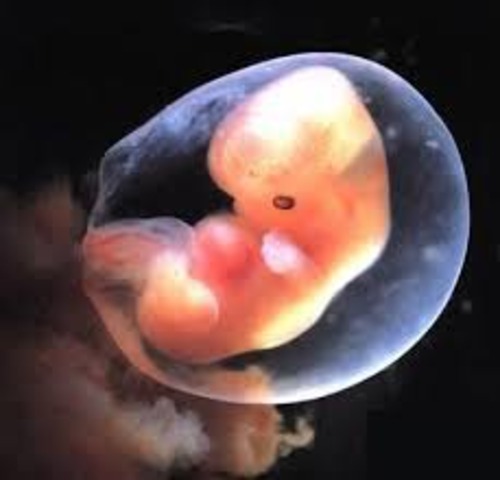

Week 6

You might be coping with full-blown pregnancy symptoms (sorry), but there's plenty of good news too. Your baby's jaw, cheeks, chin, eyes, ears, and nose are beginning to form what will eventually become one adorable face. In addition, her kidneys, liver, and lungs are developing, and her heart is now beating 80 times a minute. All this and she's still no bigger than the length of a nail head from crown to rump!